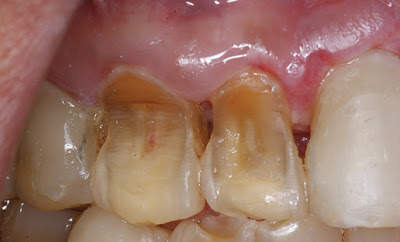

Είναι η φθορά της εξωτερικής επιφάνειας των δοντιών που οφείλεται σε χημικά αίτια. Προσβάλλεται αρχικά η αδαμαντίνη (το σμάλτο) και στη συνέχεια η υποκείμενη οδοντίνη .

Η πρόσληψη όξινων ποτών και οι εμέσεις ή εκκρίσεις του γαστρεντερικού σωλήνα προκαλούν τη διάβρωση των δοντιών.

Η διάβρωση μπορεί να είναι είτε ανώδυνη η οδυνηρή σε ζεστά ή κρύα ερεθίσματα. Μπορεί επίσης να επιπλακεί με τερηδόνα.